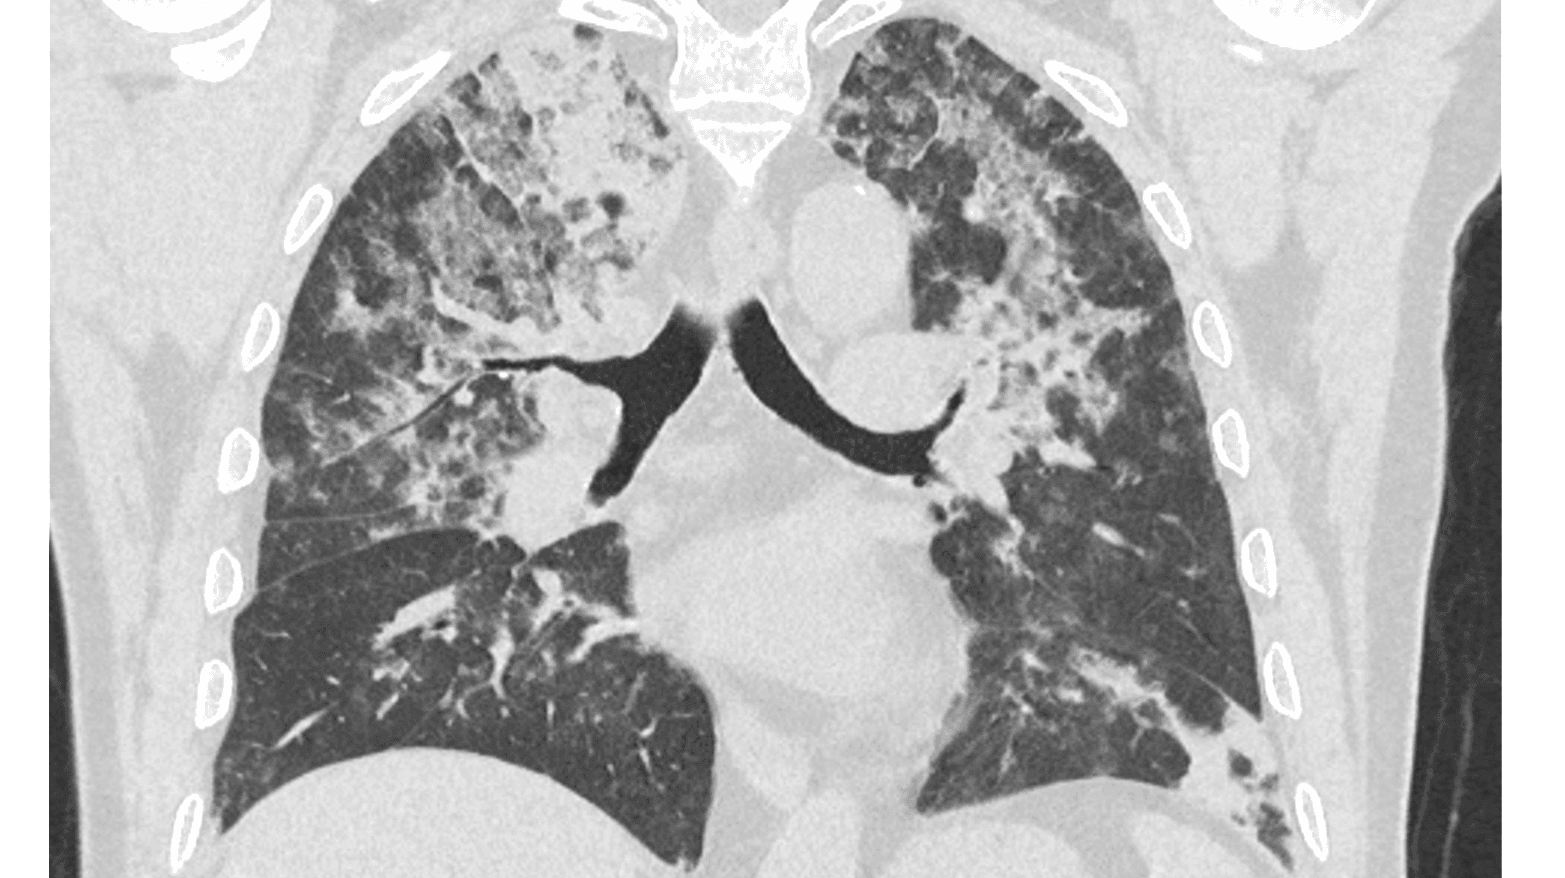

En 65-årig mand modtog første dosis af første genbehandling med immunterapi for dissemineret malignt melanom og udviklede efter to dage tiltagende åndenød, tør hoste og feber. Symptomerne progredierede hurtigt, og patienten blev indlagt seks dage efter immunterapien. På high resolution-CT af lungerne blev der konstateret udtalt immunterapiudløst pneumonitis. Efterfølgende behandling med højdosis prednisolon og ilt havde god effekt.

Denne sygehistorie illustrerer en meget hurtig udvikling af immunterapiudløst pneumonitis, også kaldet checkpoint inhibitor-pneumonitis (CIP). I et nyere studie har man vist, at incidensen var 5,1% hos immunterapibehandlede lungecancerpatienter, og anbefaler højdosis glukokortikoider som førstevalgsbehandling af CIP [1]. Eftersom immunterapi bliver en mere udbredt behandling, giver sygehistorien påmindelse om at have kendskab til denne alvorlige tilstand. Særligt udfordrende er symptombilledet på CIP, som let kan forveksles med en luftvejsinfektion [1].